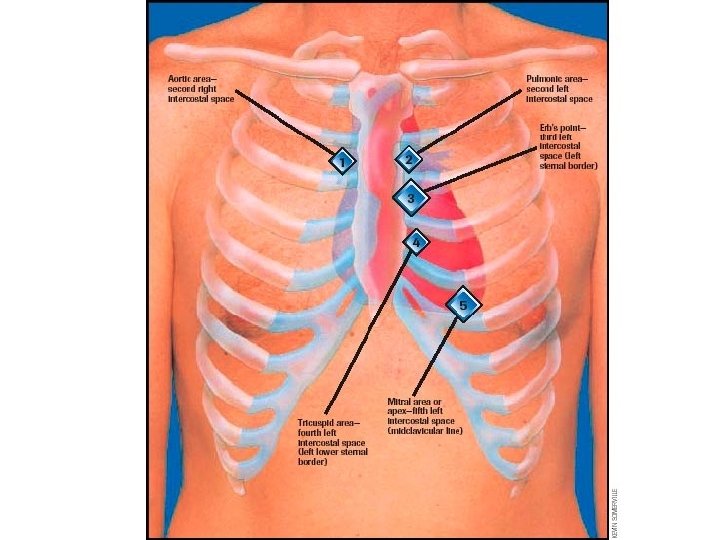

Auscultation Testut‘s points = 4 auscultation points

Auscultation – Testut´s points 4 auscultation points o Valva mitralis – 5 th intercostal space left of strenum in medioclavicular line o Valva tricuspidalis – 4 th intercostal space left (or right) of strenum o Valva aortae – 2 th intercostal space right of sternum o Valva trunci pulmonalis – 2 th intercostal space left of sternum o Erb´s point (3 rd intercostal space left of sternum) - murmurs